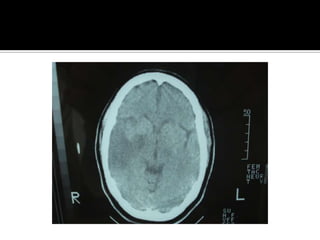

Signos tempranos:  TAC en EVC AgudoSigno dela arteria cerebral media hiperdensaAtenuacion del nucleo lenticularHipodensidad cortical o subcorticalEdema cerebralBorrado de la region insularBorrado de surcos corticalesCompresion ventricularAtenuacion de contraste cortico-medular